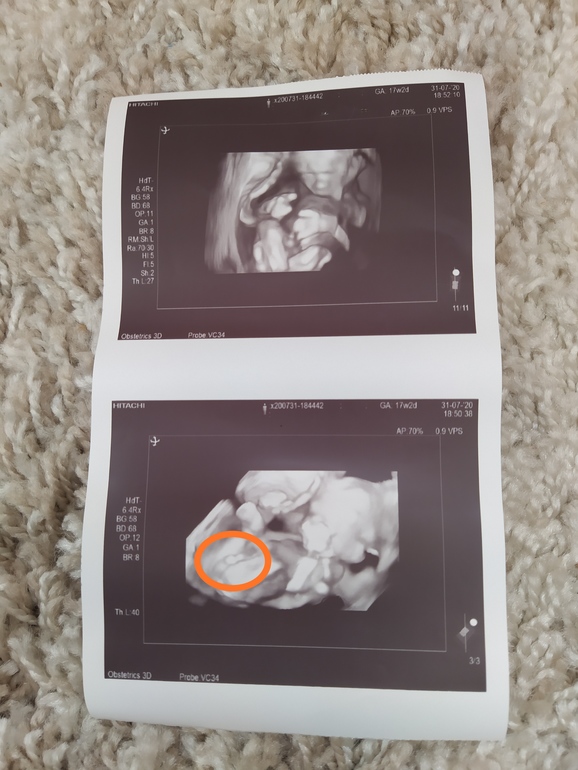

Тут на фото не особо понятно,но раз врач увидела, думаю ей виднее,с мальчиком редко ошибаются,мне вот дали фото,так тут прям четко видно,что мальчик

17+2 вчера ходила,но по фетометрии поставили 18+3,что мальчик я и так знала ещё в 12 недель ( по крови) по УЗИ подтвердили